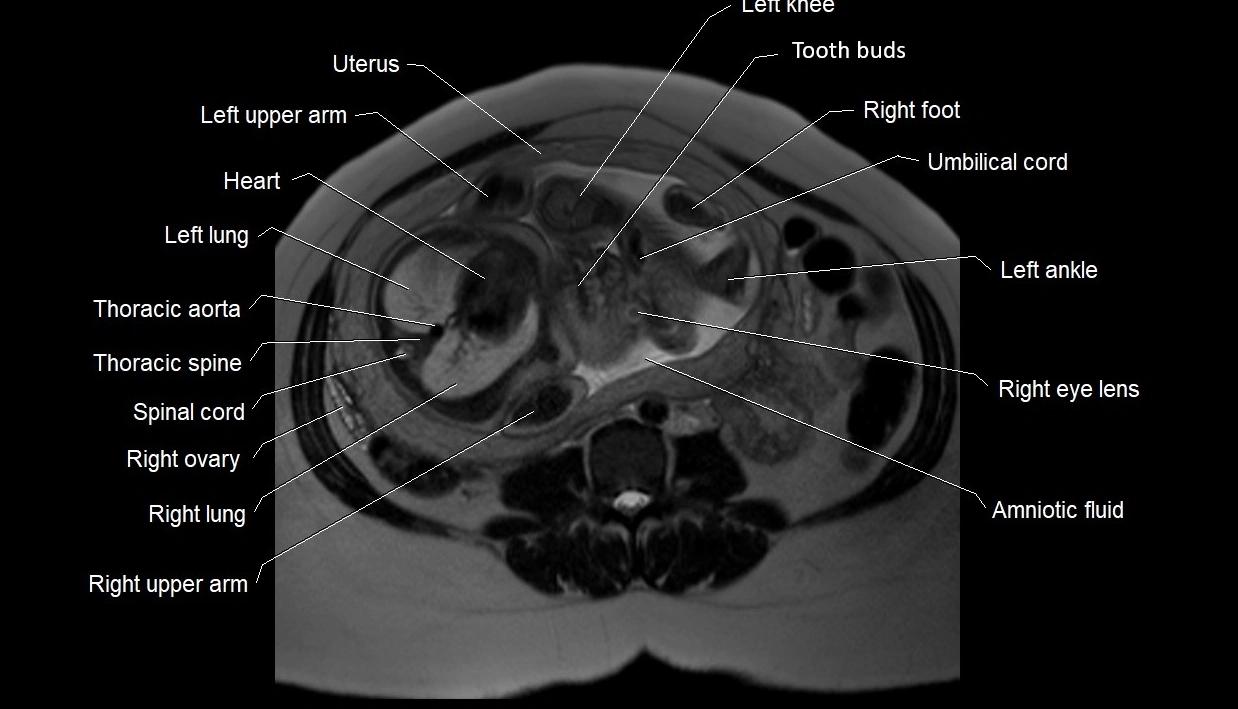

MRI Appearance

T2 HASTE (T2 GRE):

• Amniotic fluid shows very bright hyperintense signal

• Provides natural contrast against fetus and placenta

• Small particles (vernix) may appear as scattered hypointense foci within bright fluid

T1 GRE:

• Amniotic fluid shows low signal intensity (dark)

• Hemorrhage, infection, or proteinaceous content may cause focal or diffuse high signal intensity

MRI image

image